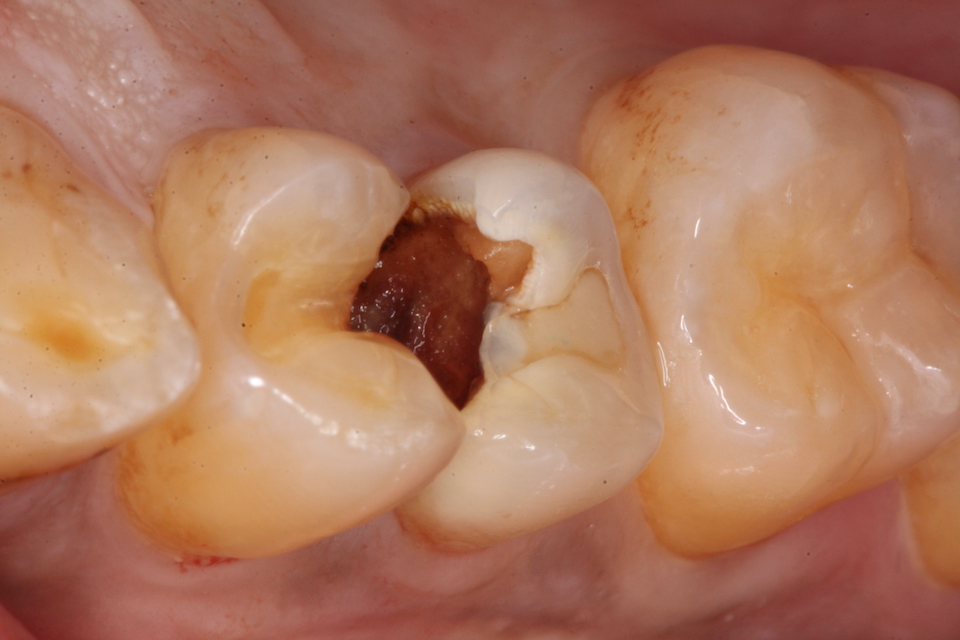

下顎7番の頬側歯茎部カリエスの原因 2025.06.04